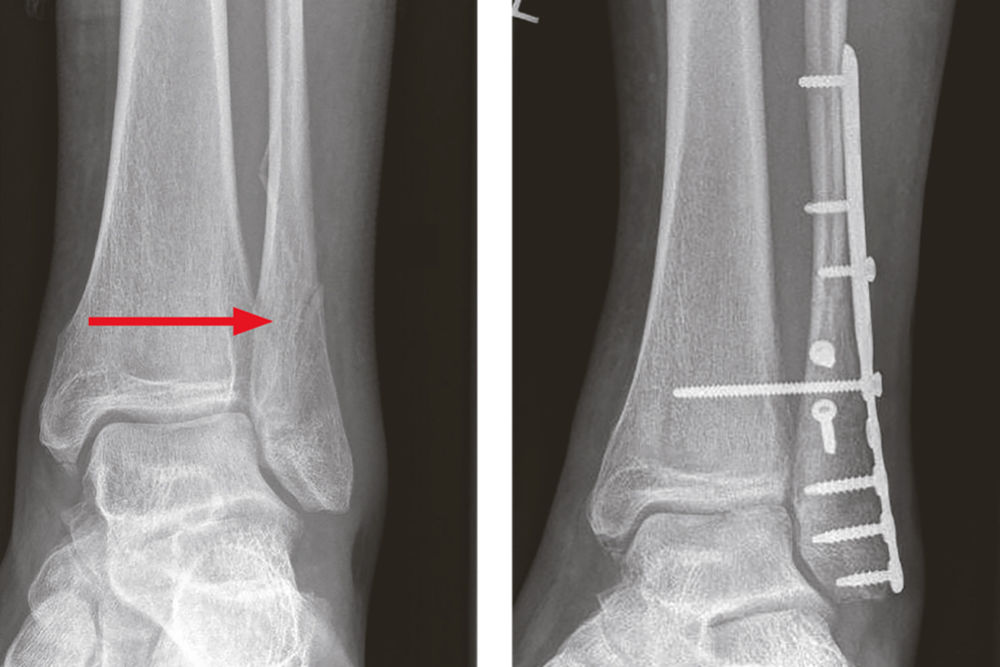

Auf Anraten der BG-Unfallambulanz wird ein 55-jähriger Patient mit anhaltenden Schmerzen im Bereich des linken Fußes und des oberen Sprunggelenks (OSG) bei Zustand nach einer Weber-C-Fraktur vorgestellt, die er sich beim Aussteigen aus einem LKW zugezogen hatte. Es erfolgte eine unmittelbare operative Versorgung mittels Schraubenosteosynthese der Fibula im März 2019.

Abbildung 2 (links): Weber-C-Fraktur am linken oberen Sprunggelenk. Abbildung 3 (rechts): Zustand nach operativer Versorgung mittels Schraubenosteosynthese

Bei den Verlaufskontrollen war ein lokaler Wundinfekt evident, sodass ein operatives Debridement über dem lateralen oberen Sprunggelenk (OSG) links erfolgte. Bei weiterhin bestehenden Wundheilungsstörungen wurde sechs Monate nach dem Unfall eine Metallentfernung durchgeführt. Im Verlauf entwickelte sich ein anhaltender, starker, brennend-stechender Schmerz im gesamten Fuß- und Sprunggelenksbereich, wobei sich die Schmerzintensität durch die Einnahme von Ibuprofen (bis 3 x 800 mg pro Tag) und Metamizol (bis 4 x 1 g pro Tag) nur wenig beeinflussen ließ.